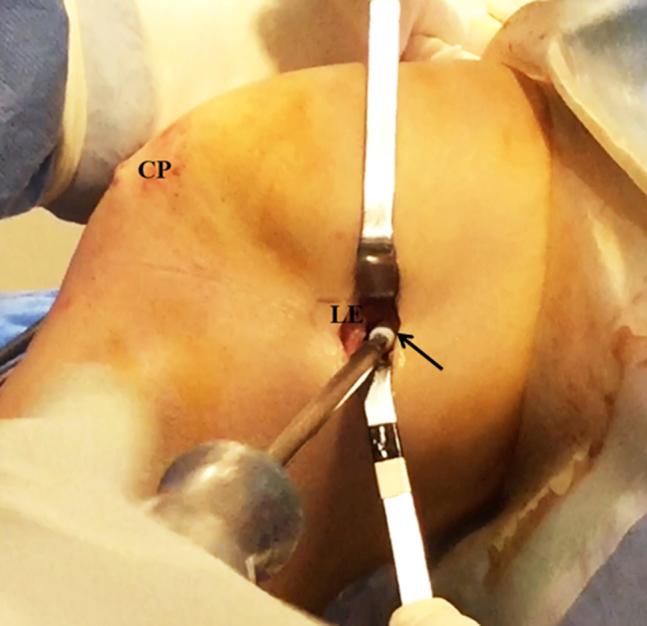

A technique for augmentation of the partial anterior cruciate ligament is presented. The patient is positioned supine with the knee flexed 90°. After addressing intra-articular injuries, the autologous semitendinosus tendon is harvested and measured in a doubled manner; after that, the tibial tunnel is performed in the outside-in direction, of the same diameter of the doubled graft. Both ends of the graft are sutured together, after inserting it through the loop of a suspension device, which is attached in its augmentation piece. A lateral femoral incision is made, to approach the joint through the "over the top" position. A looped thread is introduced inside the joint with the aid of a hook. This thread pulls the graft's sutures through the "over the top" position. A femoral tunnel is then drilled in the lateromedial and caudocranial direction. The suspension device is attached to the anterior tibial cortex and the graft is pulled in the caudocranial direction to the femoral tunnel, where an interference screw is used for fixation.

介绍了一种部分前交叉韧带增强技术。患者仰卧位,膝关节屈曲90°。处理关节内损伤后,取出自体半腱肌腱并对折测量;之后,由外向内方向制作胫骨隧道,其直径与对折后的移植物相同。将移植物两端缝合在一起,通过悬吊装置的环插入,悬吊装置连接在其增强片上。做一个股外侧切口,通过“过顶”位置进入关节。借助钩子将环形线引入关节内。该线将移植物缝线拉过“过顶”位置。然后在股骨外侧向内侧和尾颅方向钻一个股骨隧道。将悬吊装置固定在前胫骨皮质上,将移植物沿尾颅方向拉入股骨隧道,在此处使用挤压螺钉进行固定。